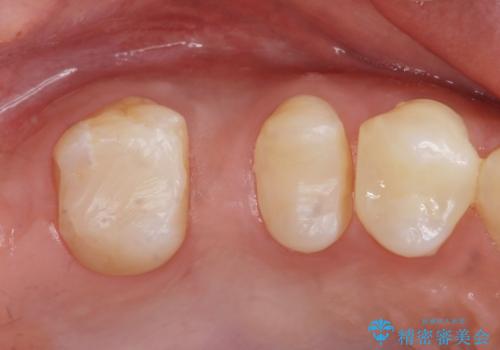

なので親知らずを抜歯して、一番奥の歯を部分矯正(upライト)をして倒れ込んでいる歯を起こしてスペースを作り、ブリッジの治療を行いました。

適合の良いブリッジが入りました。

歯の傾きを改善することにより食べ物が詰まりにくくなりました。